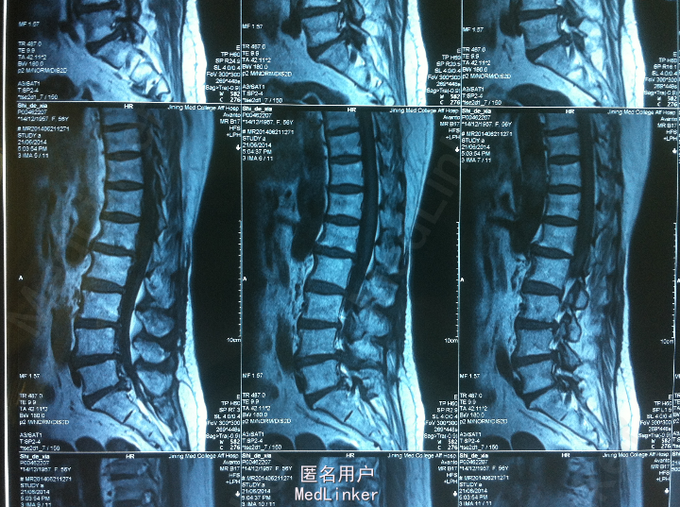

查体:腰部叩痛,腰部活动受限,左侧小腿外侧、足背感觉减退,左侧踝背伸、踇背伸、跖屈肌肌力4级,右侧踝背伸、踇背伸、跖屈肌肌力4-5级,双侧膝腱反射+,跟腱反射+,双侧巴氏征阴性。辅助检查: X-ray:腰椎退行性变节段性不稳。CT:腰椎间盘突出,腰3/4,4/5,腰5/骶1, MR:腰椎间盘突出,腰3/4,4/5,腰5、骶1椎间盘突出。

诊断:腰椎间盘突出症并节段性不稳 处理: 1、完善相关辅助检查,明确诊断,有无手术指证; 2、完善手术评估,有无手术禁忌,手术风险并发症; 3、在全麻下行腰椎后外侧入路选择性减压、横突间植骨融合内固定术

随访 术后患者下肢麻木感觉较前好转,左侧踝背伸、踇背伸、跖屈肌力4级+,术后3个月,患者下肢麻木明显好转,左侧踝背伸、踇背伸、跖屈肌肌力4-5级。应常规术后1个月、3个月、半年随访; 讨论:1、腰椎间盘突出症并节段性不稳 手术选择 PLIF VS TLIF ? 2、P-TLIF手术入路选择性减压,配合横突间植骨融合的可行性?